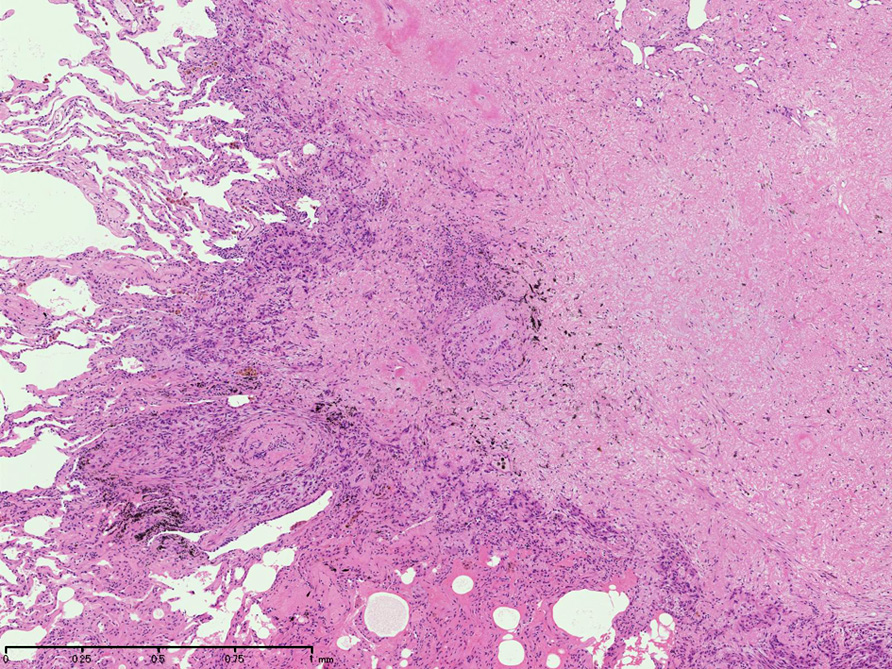

左図:腺腔様の裂隙が胞巣内にみられ, 凍結標本だと腺癌との区別がむずかしい。

右図:多型細胞や異型細胞が出現。核分裂像も異常に見える。